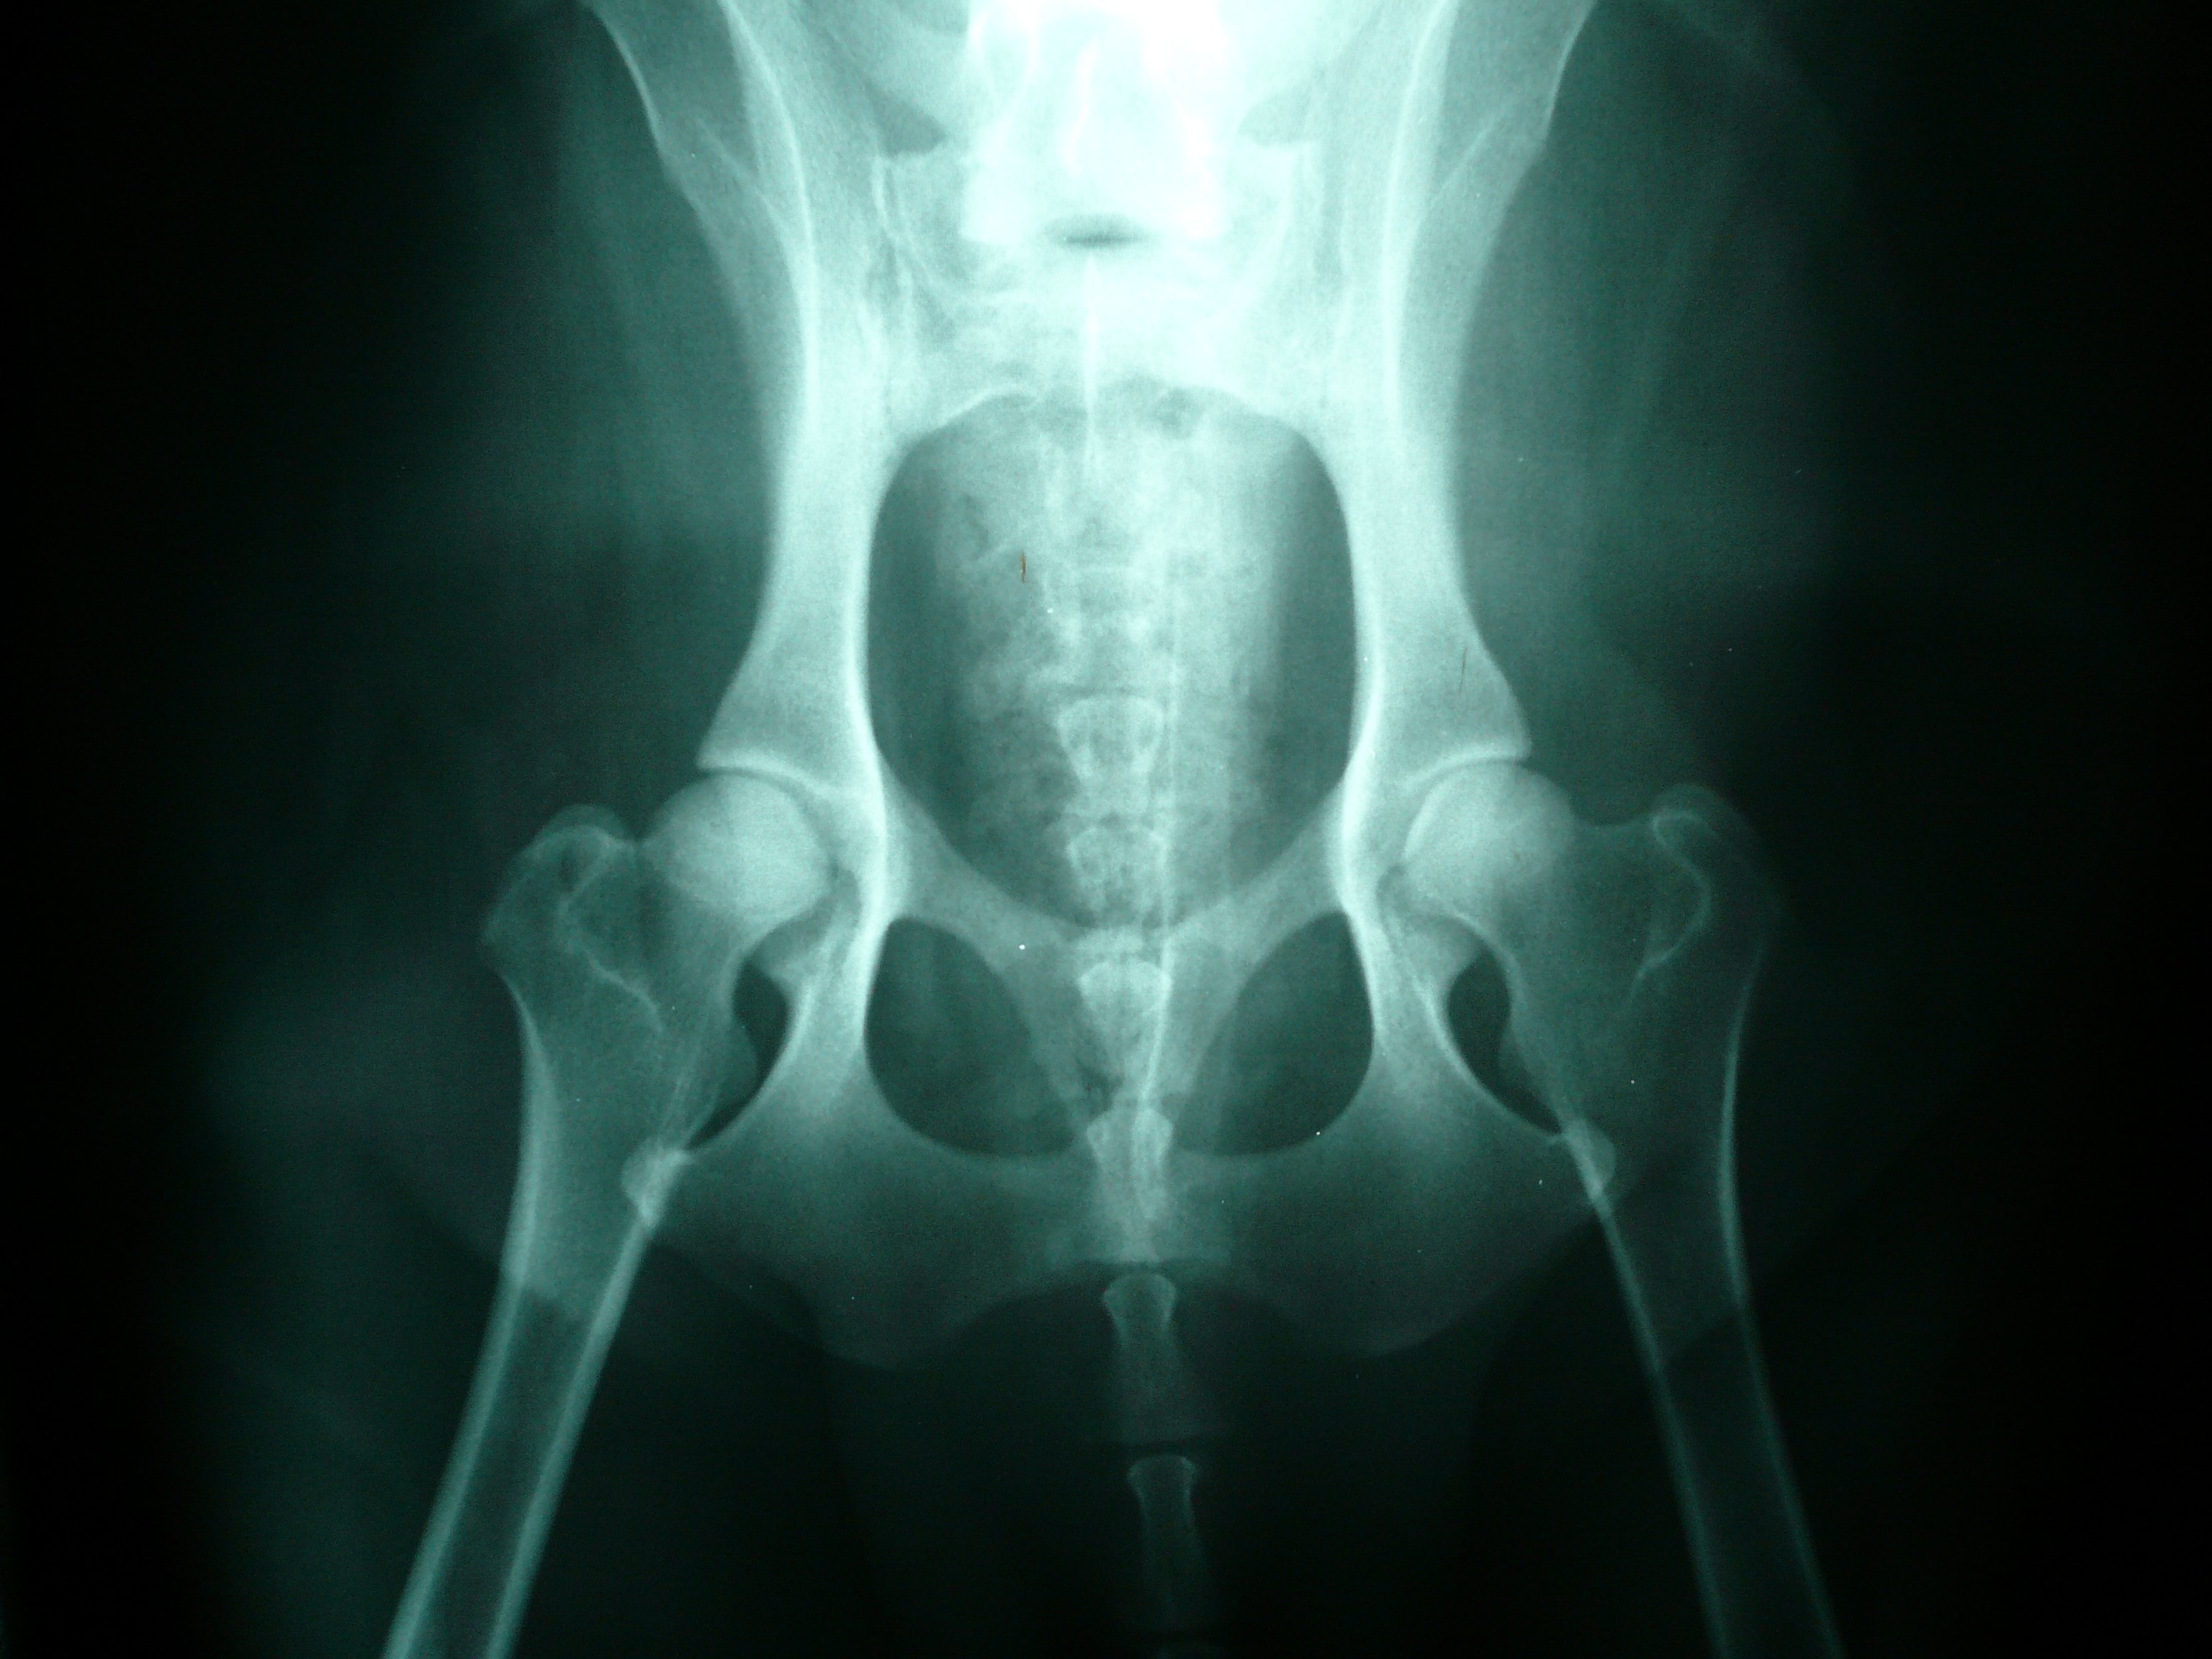

DOG HIP XRAY , PANOSTEITIS Stock Photo Image of closeup, health Normal Hip Joint In Dogs At birth, canine hip joints are normal, 112, 153 and they are thought to continue normal development if complete congruity between the femoral head and the acetabulum is maintained. Hip dysplasia causes pain, swelling, stiffness and eventually arthritis. Hip dysplasia is when the hip joints don’t fit together properly and become unstable. All you need to know about hip dysplasia. Normal Hip Joint In Dogs.

FileNormal canine hips.JPG Wikimedia Commons Normal Hip Joint In Dogs Plus, an introduction to responsible breeding practices for canine health and how to safeguard dogs from this condition. Hip dysplasia causes pain, swelling, stiffness and eventually arthritis. Dogs with hip dysplasia usually begin showing. Hip dysplasia is when the hip joints don’t fit together properly and become unstable. At birth, canine hip joints are normal, 112, 153 and they are. Normal Hip Joint In Dogs.

Normal Hips Canine xray image Normal German Shepherd Xray Image Normal Hip Joint In Dogs 2 hip dysplasia in dogs h ip dysplasia (hd) is a common inherited orthopaedic problem of dogs and a wide number of other mammals. Hip dysplasia causes pain, swelling, stiffness and eventually arthritis. At birth, canine hip joints are normal, 112, 153 and they are thought to continue normal development if complete congruity between the femoral head and the acetabulum. Normal Hip Joint In Dogs.

Normal hip xray dog rolftrac Normal Hip Joint In Dogs All you need to know about hip dysplasia in dogs, from early warning signs to treatment strategies and preventive measures. Plus, an introduction to responsible breeding practices for canine health and how to safeguard dogs from this condition. Hip dysplasia causes pain, swelling, stiffness and eventually arthritis. At birth, canine hip joints are normal, 112, 153 and they are thought. Normal Hip Joint In Dogs.